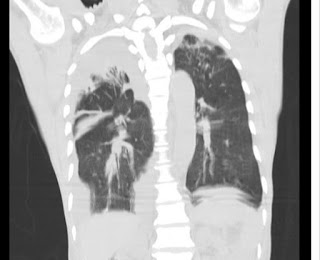

65 YEAR OLD MALE PATIENT WITH FEVER ,COUGH, SHORTNESS OF BREATH

65 year old man presented with the complaints of

Dyspnea since 4 months

Fever since 1 month

Cough since 1 month

He was apparently alright one year back after which he started to notice reduced urine output. He would often feel dyspneic after walking for a short duration since several months. Since 1 month he has been experiencing low grade fever on and off along with cough without expectoration. He also says he has been even more dyspneic over the last one month. He says he has been feeling numbness in both his lower limbs.Bilateral swelling of both his lower limbs also developed gradually extending to his knees. He also tells that there has been slippage of footwear since 1 week. He finally visited a local hospital, where in he was diagnosed with CKD with Heart failure and he received Spironolactone 50mg plus torsemide 20mg. He was even diagnosed to be a hypertensive and diabetic.

On inspection - Barrel shaped chest was present

Supraclavicular indrawing +

Intercostal indrawing +

Dullness + in Bilateral IAA, ISA

Vocal resonance reduced in right ICA,IMA,IAA,ISA

Inspiratory crepts + Bilateral IMA,IAA,ISA

decreased breath sounds+ in ISA